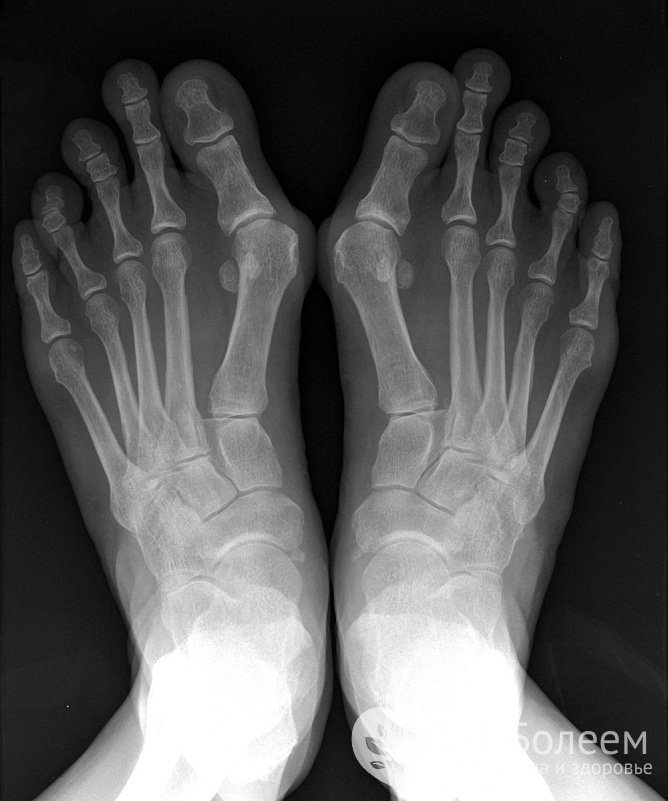

Ревматоидная стопаСуществуют две формы артрита, которые диагностируются исключительно в детском возрасте – ювенильный идиопатический артрит и ювенильный ревматоидный артрит, или болезнь Стилла. Для обоих заболеваний характерно персистирующее течение и слабый ответ на терапию, при болезни Стилла кроме суставов часто поражаются внутренние органы.

Прохождение МРТ гарантирует максимальную точность диагностики суставных патологий за счет качественной визуализации твердых и мягких тканей. Рентгенография и КТ сустава в прямой, боковой и косой проекции позволяют выявить изменения со стороны костного аппарата. Для оценки состояния хряща, сухожилий, связок, мышц и нервов дополнительно назначают УЗИ крупных суставов. При повреждении коленного сустава может потребоваться артроскопия с отбором синовиальной жидкости и биоптата. В целях отслеживания динамики процесса в отсутствие обострений может быть целесообразна контрастная артрография.

Для диагностики артрита делают рентген, МРТ или КТЛабораторная диагностика артрита предусматривает проведение общего, биохимического и иммунологического анализа крови. Высокая скорость оседания эритроцитов и повышенная концентрация фибриногена подтверждает наличие воспалительного процесса; увеличенное количество лейкоцитов – бактериальную инфекцию. При эозинофилии высока вероятность аллергической реакции. Обнаружение в сыворотке крови ревматоидного фактора наряду с превышением допустимого уровня антител и циркулирующих иммунных комплексов четко указывает на ревматоидный артрит. При подагрическом артрите повышаются показатели сиаловой и мочевой кислоты.